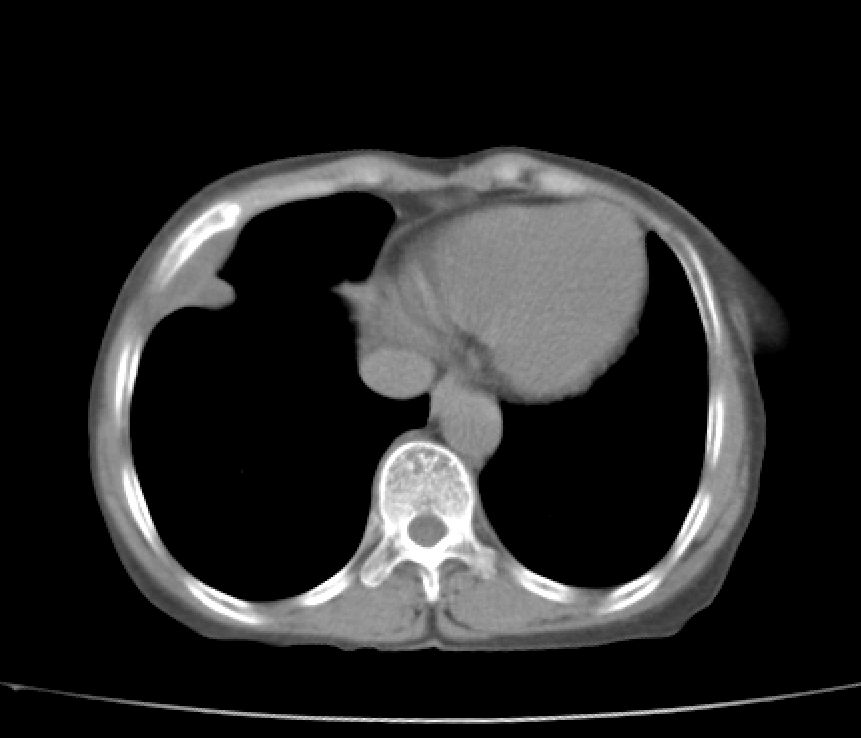

标题: CT21609:右乳包块1年,请各位讨论分析一下,乳腺CA, [打印本页]

标题: CT21609:右乳包块1年,请各位讨论分析一下,乳腺CA,

考虑---右乳癌并胸壁、肋骨、双肺转移。

考虑乳腺癌侵犯肋骨、胸壁及两肺转移可能性大。

右乳癌并胸壁、肋骨、双肺转移。

考虑右侧乳腺癌侵犯肋骨、胸壁及两肺转移。

支持考虑---右乳癌并胸壁、肋骨、双肺转移。

考虑右侧乳腺癌侵犯肋骨、胸壁及两肺转移可能。

考虑右侧乳癌并胸壁、肋骨及双肺多发性转移。